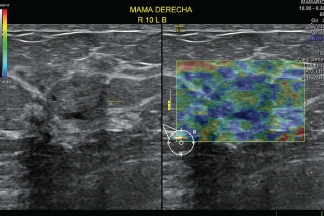

Es un tipo de prueba de diagnóstico por imagen que busca fibrosis. La fibrosis es una afección que se puede producir en MAMA, Hígado, Tiroides y Próstata entre otros.

En EDE Satélite, sabes que esta prueba es auxiliar importante en forma cuantitativa, en la clasificación de un Nódulo simple o complejo, siendo un estudio que ayuda a establecer en forma más óptima la clasificación BIRADS o TIRADS.

Se puede emplear para lesiones Nodulares Mamarias, Tiroideas, Hepáticas, Partes blandas o Músculo Esqueléticas.